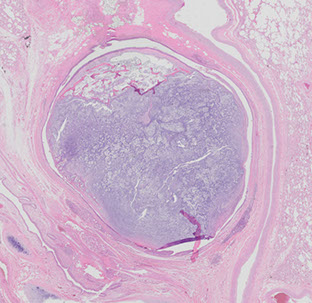

Congenital Cystic Adenomatoid Malformation (CCAM)

- aka Congenital Pulmonary Airway Malformation (CPAM; bc not all lesions cystic / adenomatoid)

Occurs equally bwt right and left lungs, and has features of immaturity and malformation of distal lung parenchyma and small airways

- usually communicate c normal tracheobronchial tree

- assoc c stillbirth, neonatal distress, bronchial atresia, and frequently hydrops

- labs can show inc aFP

Divided into 5 categories based on site of origin, from 0-4:

MC subtype is Type I: has large cysts (10 cm max) lined by a "ruffled" ciliated columnar or pseudostratified ciliated cells c interspersed mucogenic cells, broad fibrous septa, no cartilage (in 90%), no sk muscle

- type I can have lepidic growth pattern into normal adjacent lung, making it look like carcinoma

-type 3 is almost always in males and is spongy without large cysts

DDx: Bonchogenic cyst

CCAM